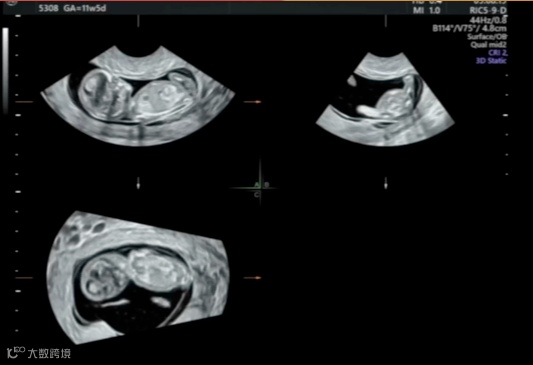

在超声机菜单上选取muti-plane、四幅画面,获得这张图。muti-plane多平面模式不同于render渲染模式,渲染模式下选择单幅画面只会显示3维图像,多平面模式就可以单独放大abc平面。

A平面是胎儿矢状切面,B平面是胎儿横切面,c平面是胎儿冠状切面。单纯旋转a切面很难获取标准正中矢状切面的,我们需要借助bc平面,只要bc平面标准了,a平面也自然是标准了。所以bc平面要选择能够快速识别是否标准的标志物,这里我选择了大脑镰,目标是b平面上大脑镰绝对垂直、c平面上大脑镰绝对平行,这样我们的a平面就是胎儿正中矢状切面了

适当放大图像,在a 平面移动观察点,让b平面容易辨认

在b平面移动观察点,让c平面容易辨认,注意b平面的观察点要放在大脑镰上,这样当b平面垂直后,才能在a平面上显示的是正中矢状切面。

在点选a平面情况下,旋转xy轴,让bc平面达到我们预期的位置,就可以看到a平面已经基本显示出正中矢状切面了。